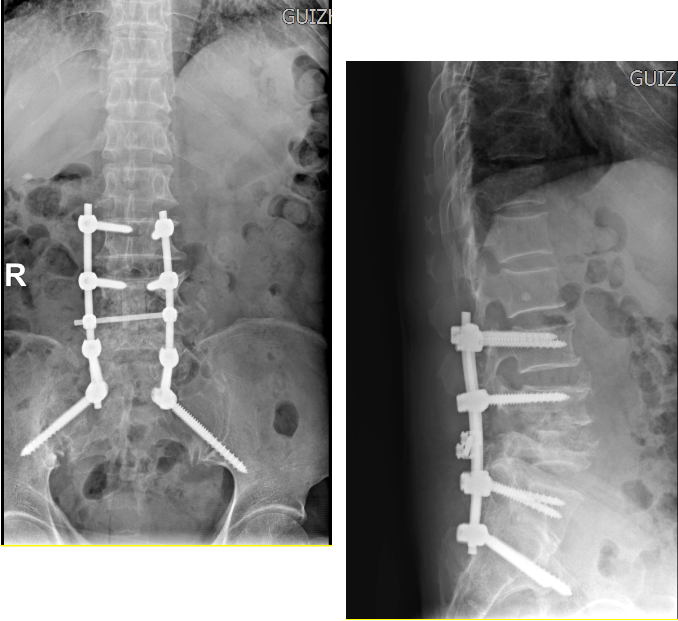

近日,六盘水市第二人民医院脊柱外科团队完成了1例高难度“腰椎结核病灶清除、椎间植骨融合内固定术”。该手术首次采用徒手S2AI螺钉内固定方式,标志着六盘水市第二人民医院脊柱外科治疗水平又上新台阶。

患者63岁,因“腰痛8年,加重伴双下肢痛麻4月”入院,保守治疗无缓解后前来医院脊柱外科就诊,经详细问诊和细致查体,结合影像学资料,诊断:1.腰椎结核并椎旁脓肿;2.腰椎椎管狭窄症。经规范抗结核治疗后,医院脊柱外科团队对该患者实施“腰椎结核病灶清除、椎间植骨融合术”。术中由于腰5椎体破坏严重,椎弓根螺钉无法置入,远端需固定到骨盆提供坚强的脊柱稳定。S2AI螺钉技术作为腰骶骨盆理想的固定方式,首次在医院开展,目前患者术后恢复良好。(六盘水市第二人民医院)